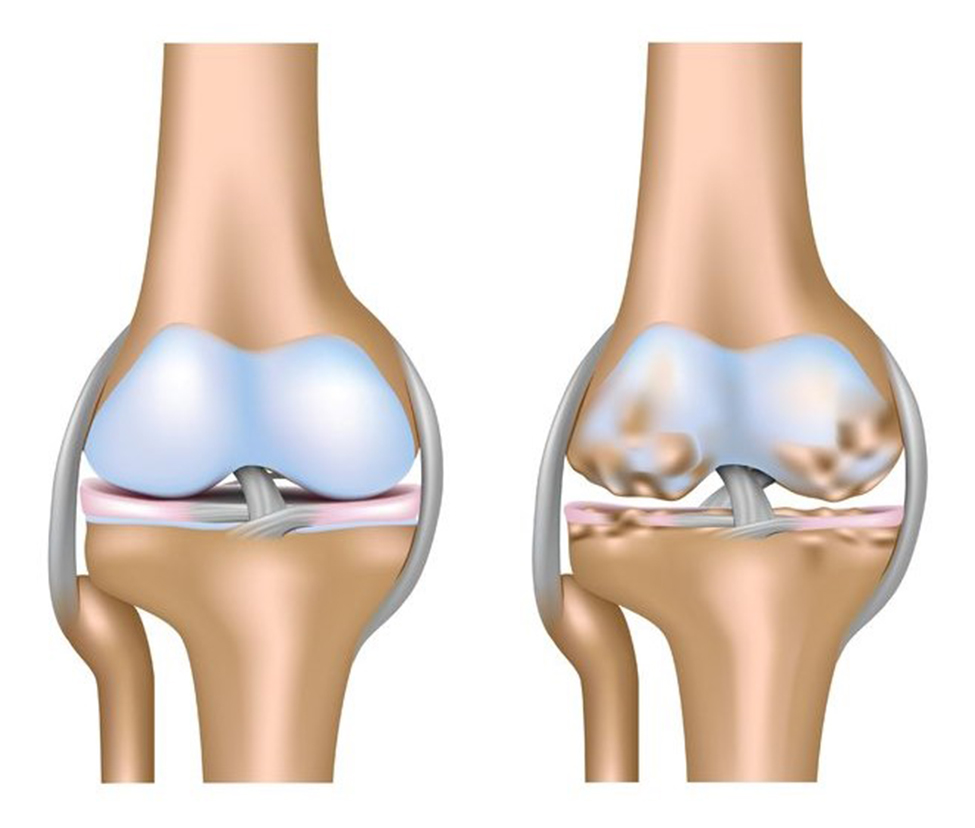

Phục hồi chức năng bệnh lý cơ xương khớp